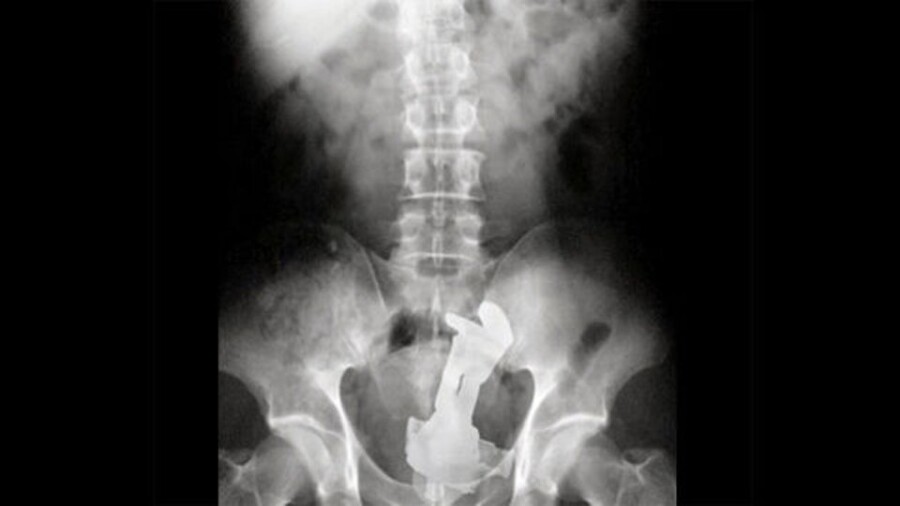

Dildos and butt plugs, accounting for more than 40 percent of cases in sexual-pleasure accidents, were the most commonly lodged objects found in a study that sifted through seven years of records involving 73 patients at a Stockholm hospital.

A "safety string or adequate-sized stopper" could have prevented many of the affected patients from retaining the sex toys, the authors said.